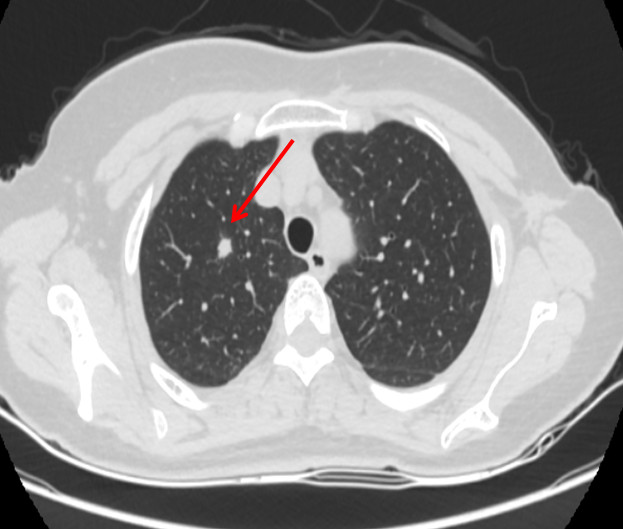

2015-09乳腺超声提示左腋窝淋巴结转移;穿刺病理为浸润性导管癌;胸部CT示左腋窝淋巴结转移,右肺上叶间尖段、左肺下叶前基底段多发转移。上腹CT及骨扫描未见异常。